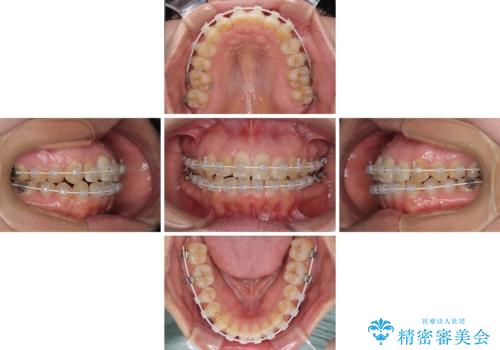

治療開始後すぐに妊娠され、つわりと闘いながらの矯正治療となりました。

上下顎でゴムかけを行ったのですが、早く終わらすためにしっかりと装着していただき、無事出産前に装置を外すことができました。